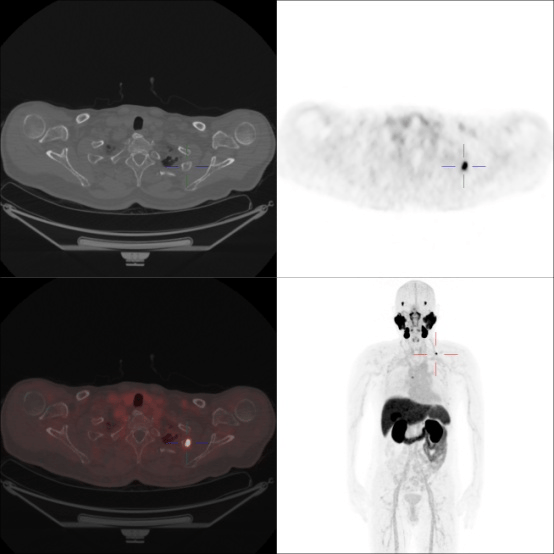

病例二

患者,男,72岁,前列腺癌术后7年余,连续3次tPSA>0.2ng/ml

左侧第2肋、T6椎体PSMA摄取增高灶,考虑转移瘤